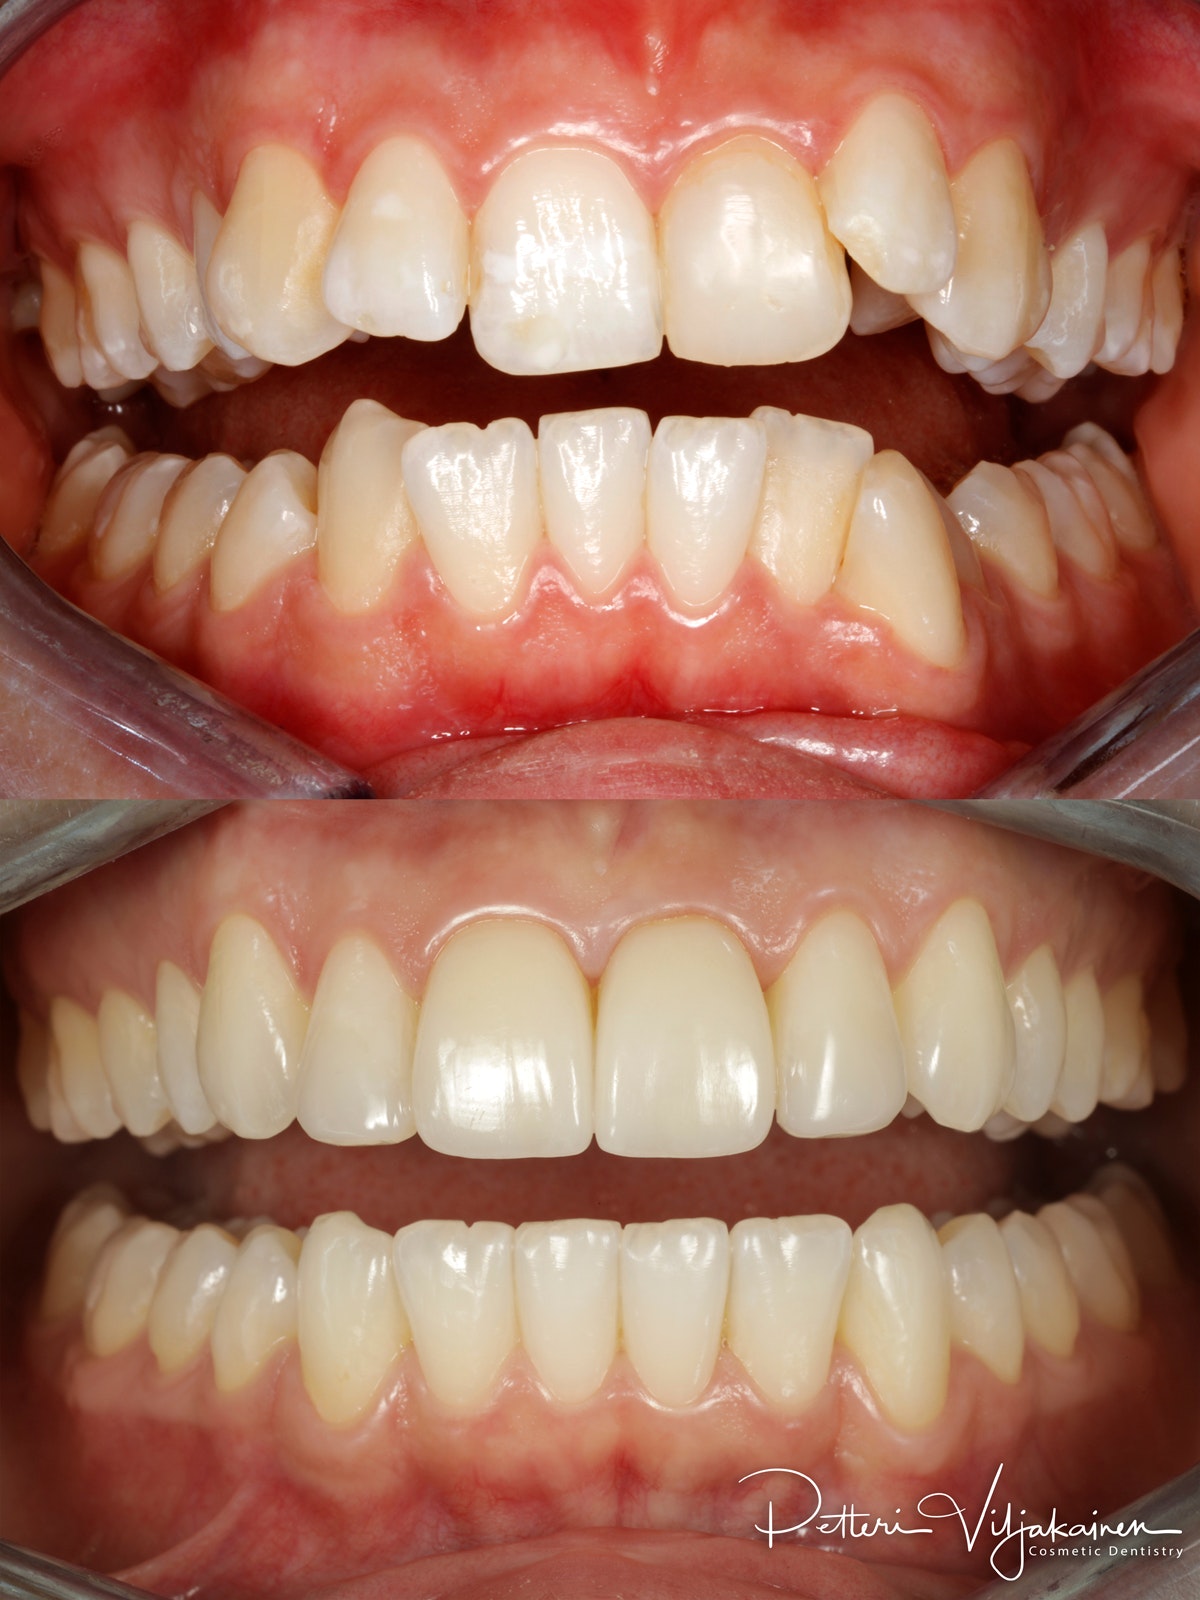

18kk hoito (Comprehensive). Keraamiset kuoret keskimmäisiin yläetuhampaisiin, kerrostusmuoveilla tehty reunimmaiset yläetuhampaat.